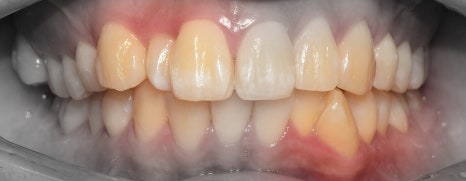

이 분은, 돌출입의 정도가 심했기 때문에

정면에서 본 모습에서도 입술의 긴장감이

같이 느껴지는 분입니다.

그리고, 구치부의 교합력이 다른 사람보다

더 높으신 분이였습니다.